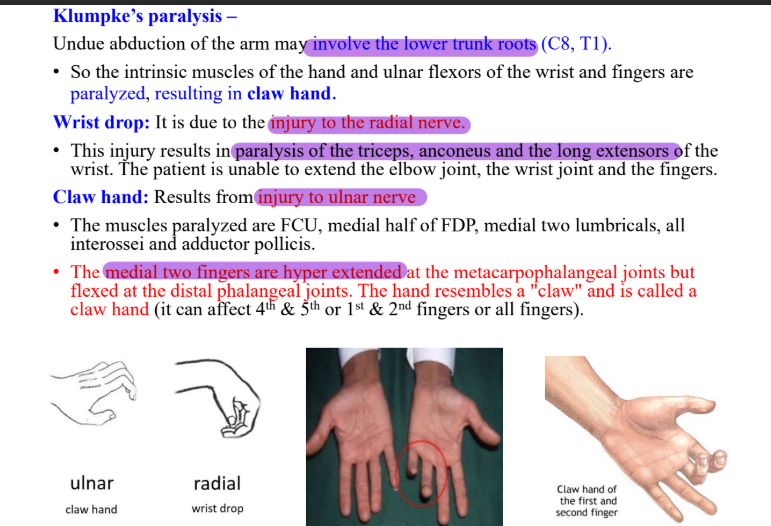

Clinical anatomy of brachial plexus